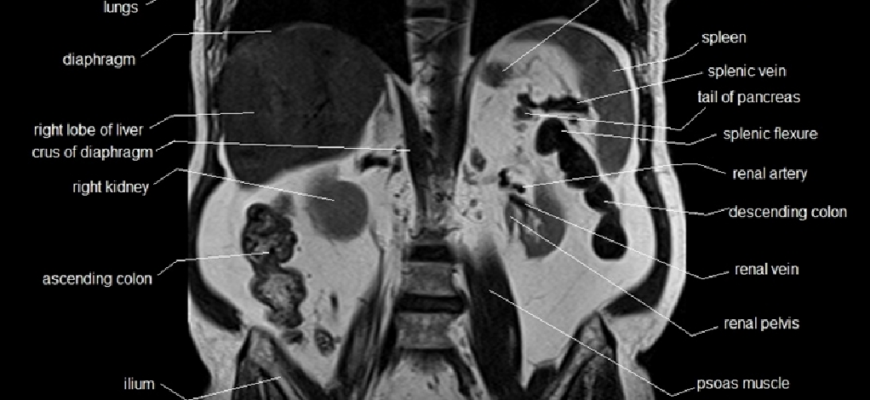

Магнитно-резонансная томография органов брюшной полости — современный метод диагностики, позволяющий визуализировать анатомическое строение органов брюшной полости и забрюшинного пространства.

Магнитно-резонансная томография брюшной полости указывает на наличие объемных опухолей, их размер и точное расположение. Приводятся точные размеры паренхиматозных органов (печень, селезенка, поджелудочная железа, почки) и записываются смещения положения органов. Таким образом, описана плотность паренхиматозных тканей, принят характер жидкого содержимого кистозных новообразований (общая киста, эхинококковая киста, абсцесс, гемангиома).

Ангиографическое исследование показывает аномальное развитие сосудов, отсутствие или гипоплазию магистральных сосудов, анатомические патологические стриктуры (коарктация, стеноз) и выпячивание сосудистой стенки (аневризмы).